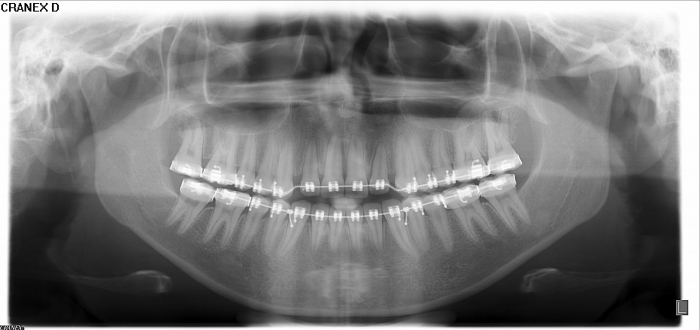

Raio - x Inicial - Clínica Cliniface

Raio - x Inicial